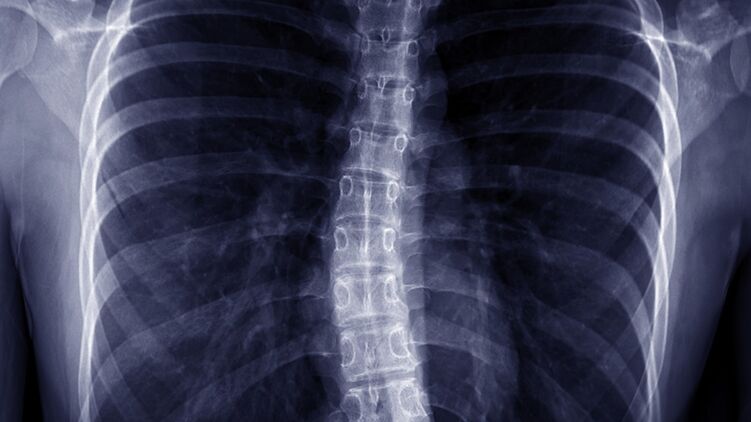

Этот недуг характеризуется S или C образным искривлением позвоночника в боковой плоскости. Человек может выглядеть так, будто он наклоняется в одну сторону. При этом могут поражаться как грудной, так и поясничный отдел позвоночника.

С увеличением искривление растет тенденция к ухудшению проблем общего состояния здоровья. Сильные сколиозы является причиной деформации туловища и его укорочения и приводят к уменьшению объема грудной клетки и брюшной полости.

- заметно изогнутый позвоночник, склонен в одну сторону

- одно плечо выше другого

- одна лопатка выступает больше, чем вторая

- асимметрия треугольника талии

- одно бедро выше другого

- неравномерность формы грудной клетки сзади при наклоне туловища вперед

- выпячивание ребер с одной стороны

- при тяжелых формах грудная клетка может сдавливать легкие и сердце, что затрудняет дыхание и сердечную деятельность